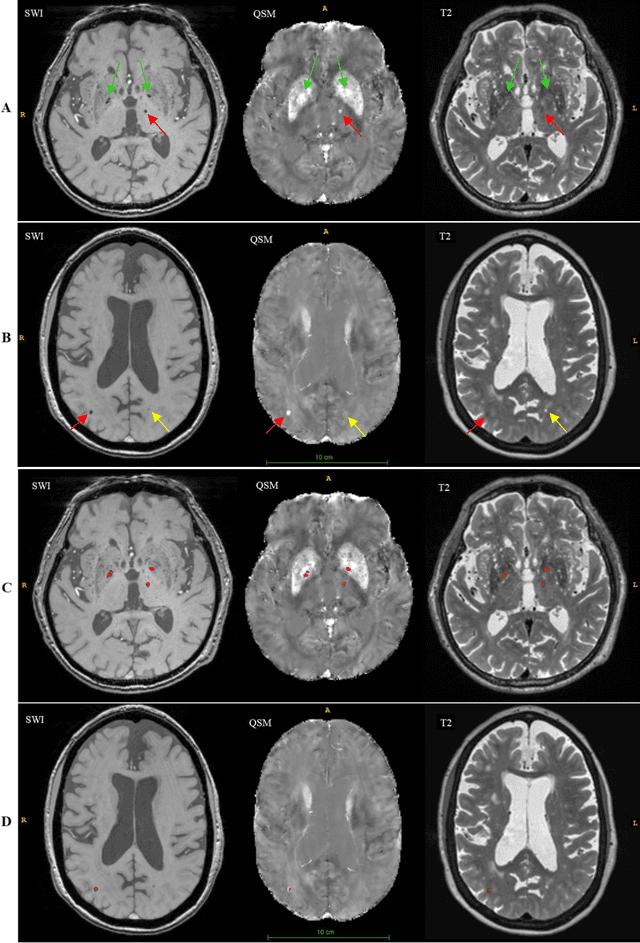

Abstract:Background: Cerebral microbleeds (CMBs) and non-hemorrhage iron deposits in the basal ganglia have been associated with brain aging, vascular disease and neurodegenerative disorders. Recent advances using quantitative susceptibility mapping (QSM) make it possible to differentiate iron content from mineralization in-vivo using magnetic resonance imaging (MRI). However, automated detection of such lesions is still challenging, making quantification in large cohort bases studies rather limited. Purpose: Development of a fully automated method using deep learning for detecting CMBs and basal ganglia iron deposits using multimodal MRI. Materials and Methods: We included a convenience sample of 24 participants from the MESA cohort and used T2-weighted images, susceptibility weighted imaging (SWI), and QSM to segment the lesions. We developed a protocol for simultaneous manual annotation of CMBs and non-hemorrhage iron deposits in the basal ganglia, which resulted in defining the gold standard. This gold standard was then used to train a deep convolution neural network (CNN) model. Specifically, we adapted the U-Net model with a higher number of resolution layers to be able to detect small lesions such as CMBs from standard resolution MRI which are used in cohort-based studies. The detection performance was then evaluated using the cross-validation principle in order to ensure generalization of the results. Results: With multi-class CNN models, we achieved an average sensitivity and precision of about 0.8 and 0.6, respectively for detecting CMBs. The same framework detected non-hemorrhage iron deposits reaching an average sensitivity and precision of about 0.8. Conclusions: Our results showed that deep learning could automate the detection of small vessel disease lesions and including multimodal MR data such as QSM can improve the detection of CMB and non-hemorrhage iron deposits.